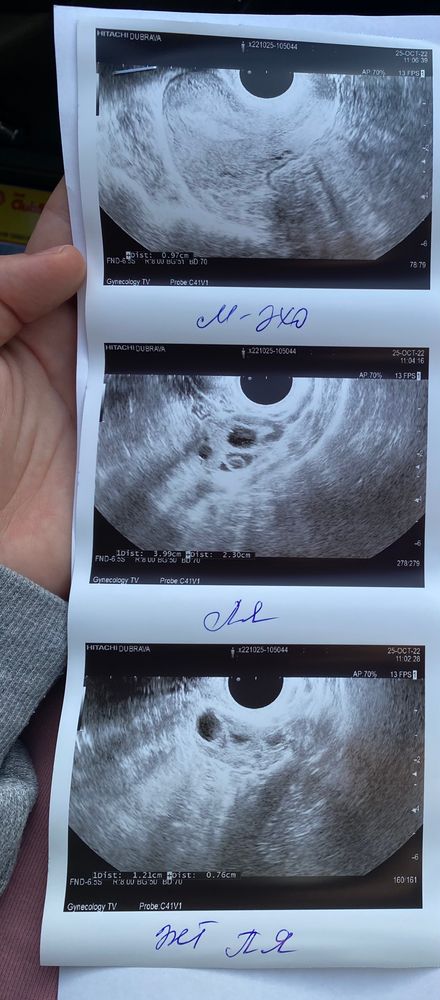

Узи на 6 дпо

Овуляция была- это хорошо. Но ЖТ откровенно говоря маленькое (и неправильной формы) для 6 ДПО. У вас либо овуляция была значительно позже, незадолго до УЗИ, либо ЖТ уже регрессирует.

Овуляция была. Написано, что есть желтое тело. Так же яичники мультифолекулярные…не приговор, беременеть с ними можно, главное следить за овуляцией, цикл может быть длиннее обычного.

О была: желтое тело и жидкость. удачи 🍀